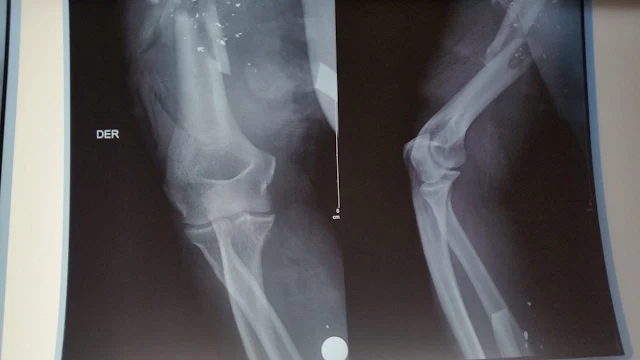

En cuanto a las lesiones óseas, el policía sufrió fractura fragmentada de húmero y radio.